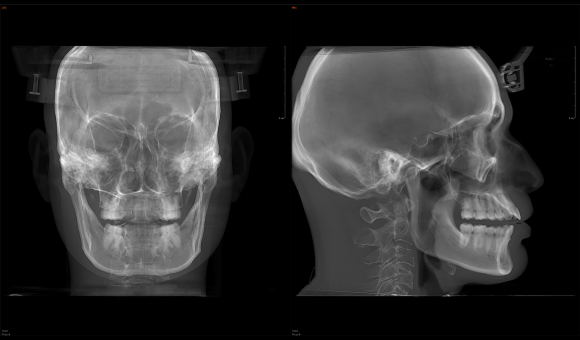

实现3D“一成三”成像

单圈扫描可同时获得CT、3D全景及3D正侧位影像,患者无需多次摆位。